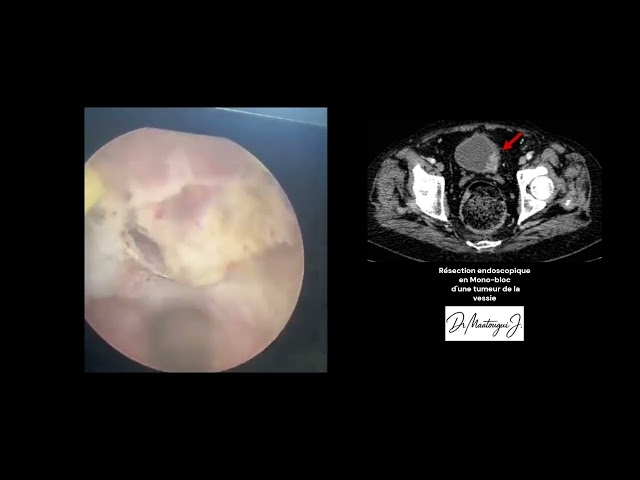

Le Dr Jasser Maatougui est un chirurgien urologue exerçant à Ben Arous. Il est spécialisé dans le diagnostic et le traitement chirurgical des affections de l’appareil urinaire et génital chez l’homme et la femme. Il pratique notamment la chirurgie des varicocèles, la résection de la prostate, le traitement des calculs urinaires au laser, la chirurgie de l’adénome prostatique, la pose de prothèses péniennes et le traitement des cancers urologiques. Le Dr Maatougui parle arabe, français et anglais, et reçoit ses patients au Centre Médical Phoenix du lundi au samedi. Les rendez-vous peuvent être pris en ligne via ce site.

Ancien médecin spécialiste en Chirurgie Urologique à l’hôpital des forces de sécurité de l’intérieure à La Marsa, Spécialiste en Chirurgie Urologique et Sexologique.